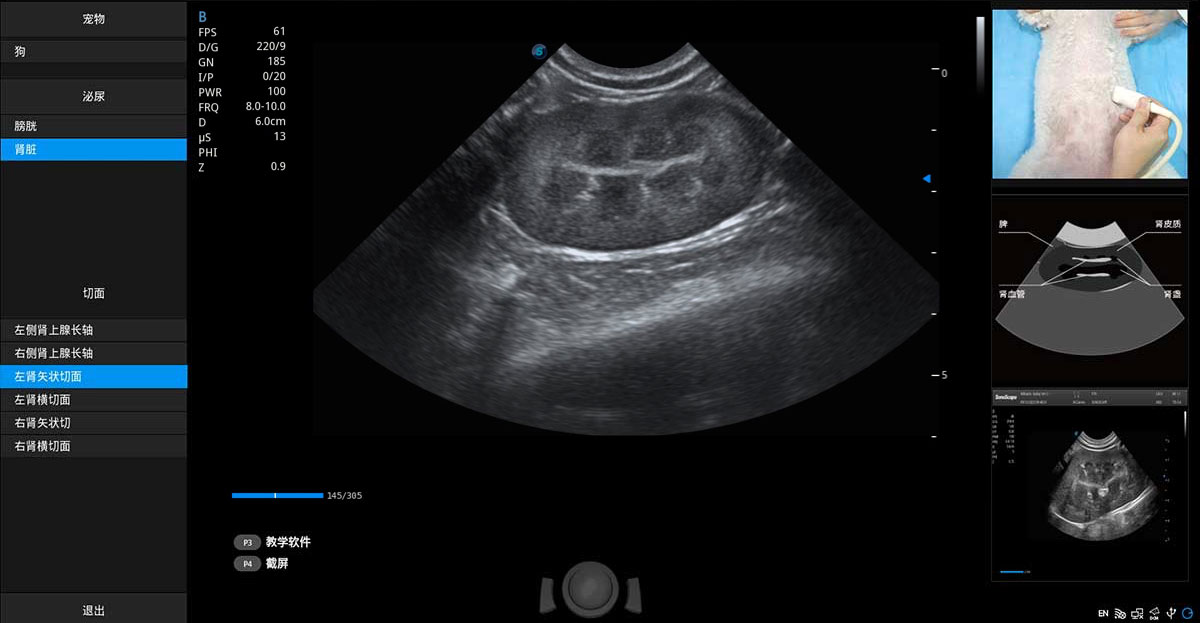

ProPet 70專為動物醫(yī)生設(shè)計,對不同的動物體型和生理結(jié)構(gòu)作出了針對性的優(yōu)化。通過動物影像專用軟件,可滿足個性化的應(yīng)用需求,幫助動物醫(yī)生獲得更精確的診斷數(shù)據(jù)。

提供解剖示意圖、標準超聲圖像、掃查手法圖和操作者實時檢查圖像,指導(dǎo)操作者進行標準切面的正確掃查。

針對寵物、馬科、農(nóng)場動物、實驗室動物和異寵等20多種動物種類,預(yù)置豐富的動物注釋及動物體標庫。